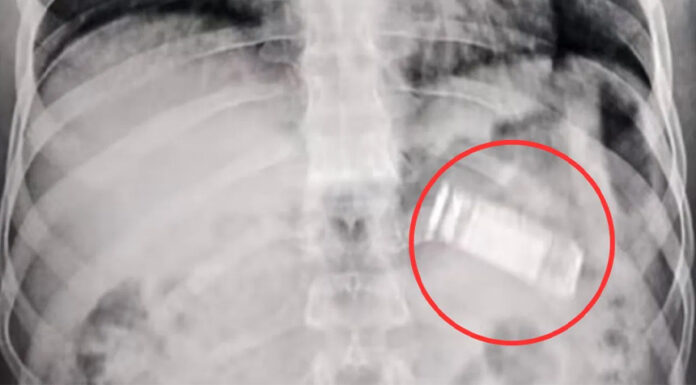

রেড সি হেলথ ডিরেক্টরেটের মতে, অজ্ঞাত ওই রোগী তীব্র পেটে ব্যথা, ক্রমাগত বমি এবং ক্লান্তি নিয়ে হাসপাতালে এসেছিলেন। ইমেজিং স্ক্যানে একটি বস্তু পাকস্থলিতে বাধা সৃষ্টি করে বলে দেখা যায়। পরে সার্জনরা সেটিকে চিহ্নিত করেন। মূলত ভুলবশত মোবাইল ফোনটি গিলে ফেলেছিলেন ওই রোগী।

হাসপাতালের পরিচালক ডা. করিম এল শাবরাভি সাংবাদিকদের জানিয়েছেন, একটি বিশেষায়িত মেডিকেল দল ডিভাইসটি অপসারণের জন্য একটি জরুরি প্রক্রিয়া সম্পাদন করেছে। অস্ত্রোপচারটি কোনো জটিলতা ছাড়াই সম্পন্ন হয়েছে এবং রোগী জ্ঞান ফিরে পেয়েছেন, যদিও তিনি পর্যবেক্ষণে রয়েছেন। তবে ডিভাইসটি কীভাবে সেখানে শেষ পর্যন্ত পৌঁছেছে তা বিস্তারিতভাবে জানানো হয়নি। রোগী সম্পর্কেও বিস্তারিত কিছু জানা যায়নি।